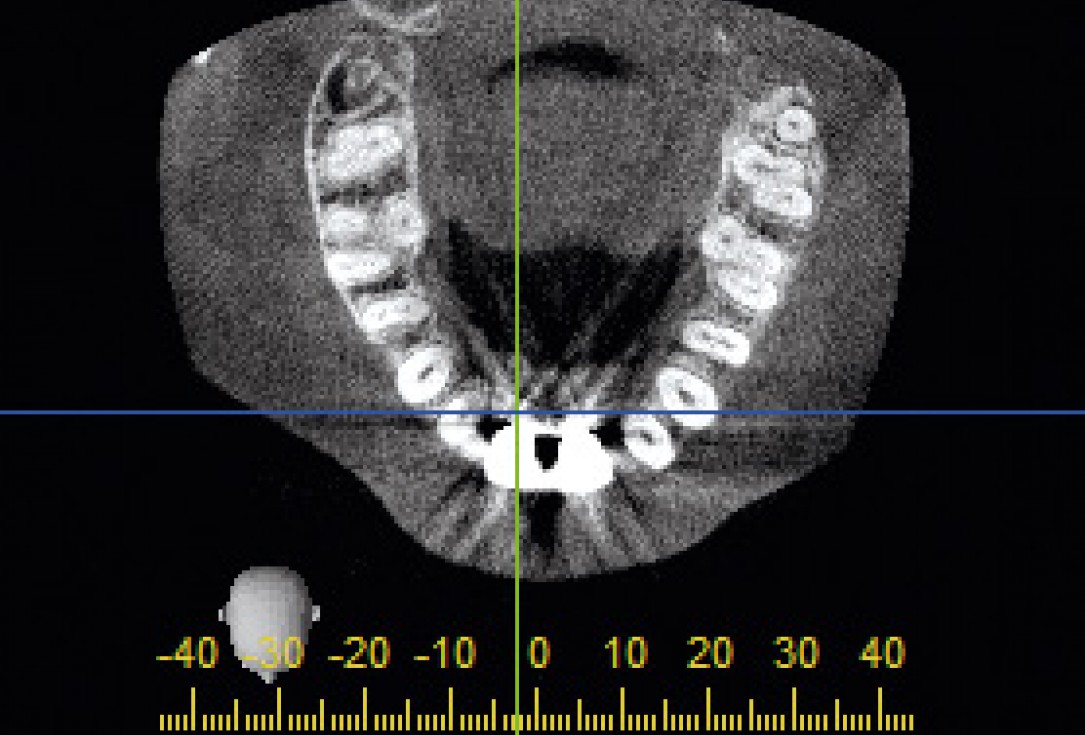

2/26 - CT scan reveals major bone loss in frontal maxillaBone augmentation in aesthetic zone with maxgraft® bonering - Dr. A. Patel

24/26 - CT scan after implants been restoredBone augmentation in aesthetic zone with maxgraft® bonering - Dr. A. Patel